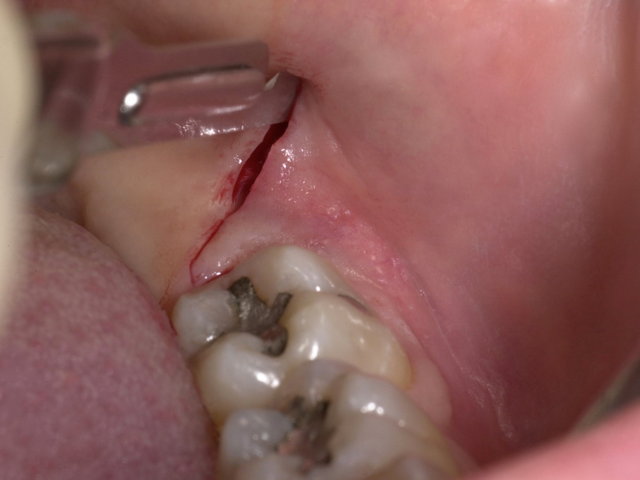

Operative Weisheitszahn-Entfernung ... ✓